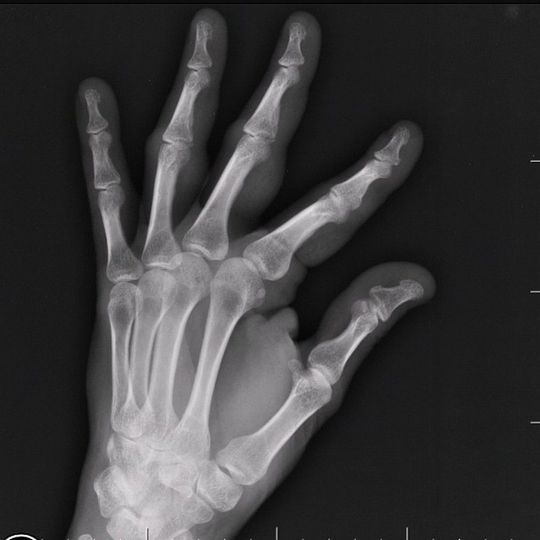

Swelling and tenderness of 3rd and 4th fingers of the left hand after a soccer ball trauma to finger tips.

It seems there is a fracture in the apex of the second phalang of 3 and 4th finger

Since it is injury, it is displacement of the 3rd and 4th phalanges.